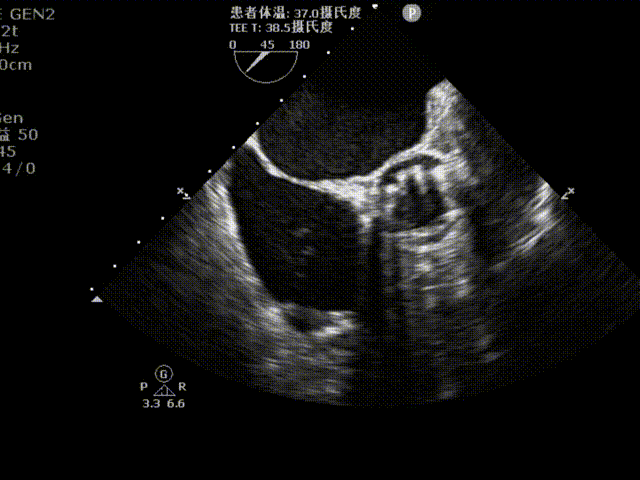

术后超声评估

植入后超声多切面评估,瓣膜位置理想,血流动力学改善显著。